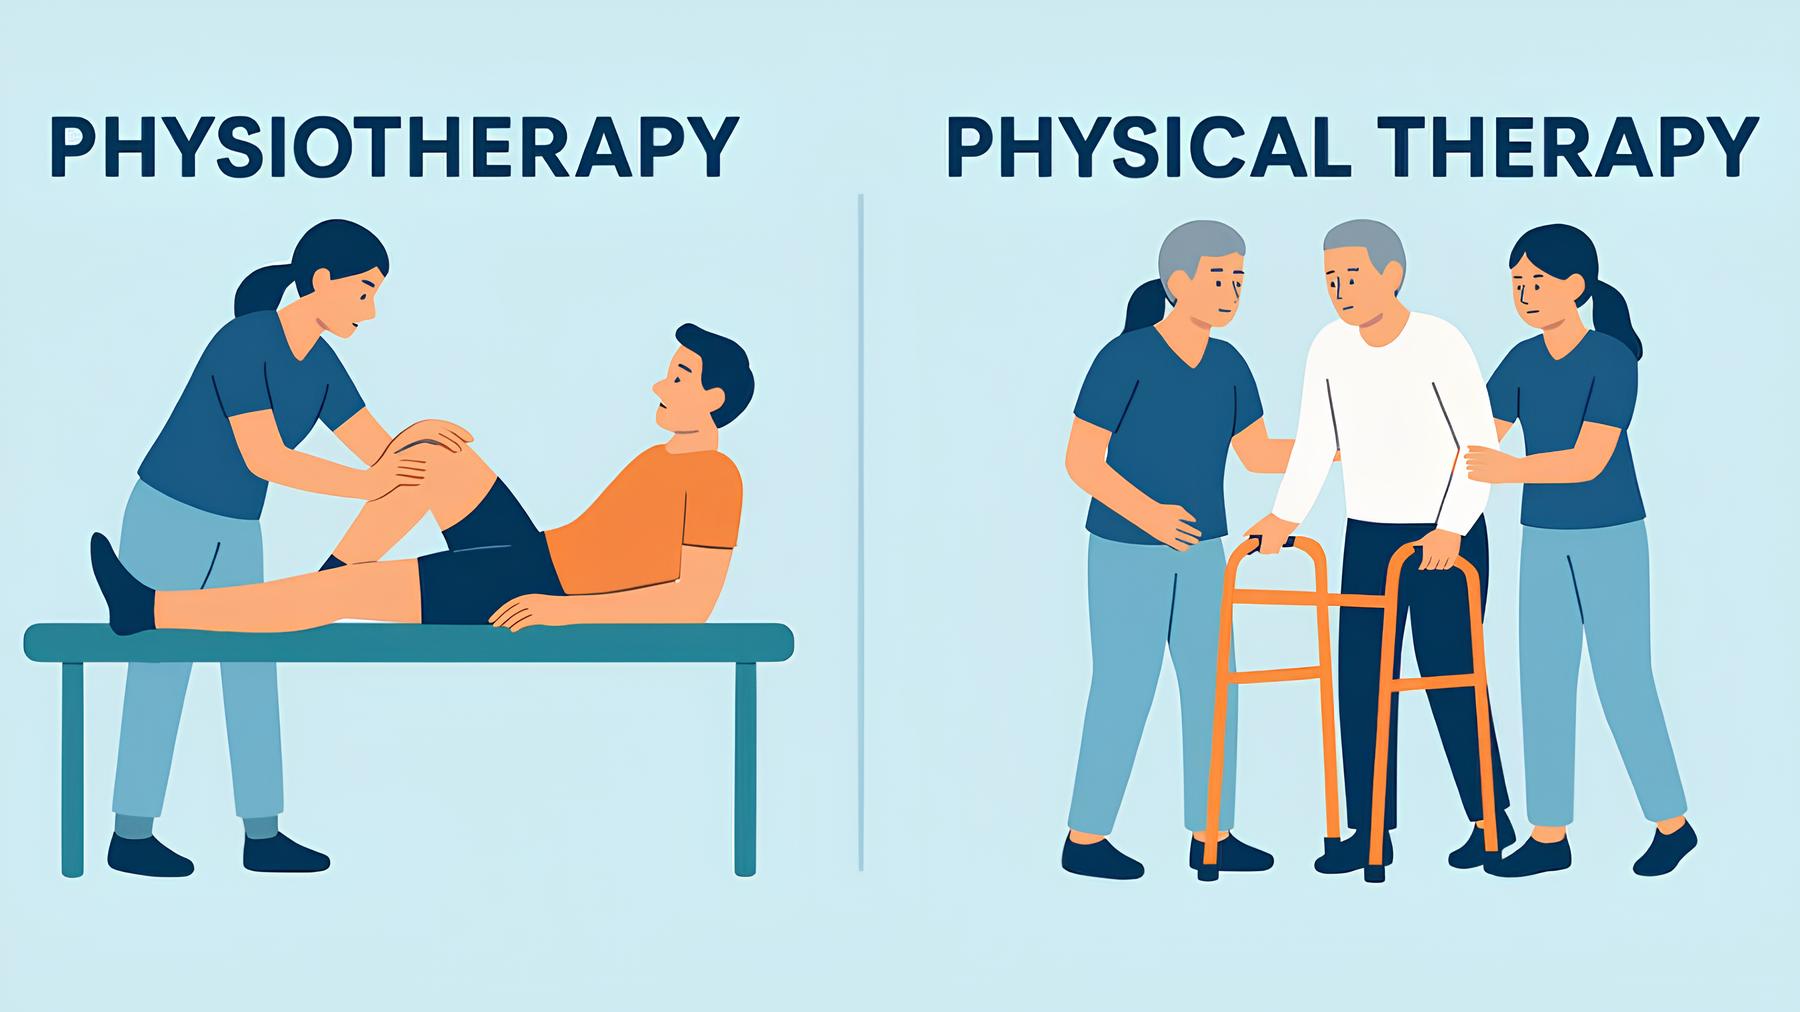

درمان آرتروز

درمان استئوآرتریت معمولاً شامل ترکیبی از فیزیوتراپی، ورزش درمانی، داروها و تغییرات سبک زندگی است. فیزیوتراپیست ها می توانند شما را در تمریناتی راهنمایی کنند تا عضلات اطراف مفاصل را تقویت کرده و انعطاف پذیری را افزایش دهند و در عین حال درد را کاهش دهند.

درمان بدون جراحی آرتروز

درمان های فیزیکی و وسایل کمکی

فیزیوتراپیست ها، کار درمانگران و متخصصان کایروپراکتیک می توانند در زیر برای درمان آرتروز کمک کنند.

- فیزیوتراپی و کار درمانی

- تمرینات خاصی برای کمک به تثبیت مفاصل و کاهش درد

- اطلاعاتی در مورد درمان های طبیعی که می توانند درد را کاهش دهند.

- دستورالعمل برای سهولت حرکت و محافظت از مفاصل

- اطلاعات و راهنمایی در مورد بریس، کفش، کفی یا سایر وسایل کمکی

- طب سوزنی یکی از درمان های فیزیکی موثر برای کاهش درد زانو در کوتاه مدت در نظر گرفته شود.

- از تحریک الکتریکی(TENS) و التراسوند (US) نیز می توان برای مدیریت درد و بهبود بافت استفاده کرد.

فیزیوتراپی و توانبخشی

- تقویت عضلات اطراف مفصل

- حفظ یا افزایش دامنه حرکتی مفصل

- کاهش خشکی و پیشگیری از ناتوانی حرکتی